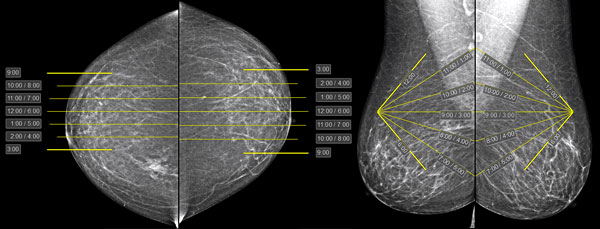

The tool allows marking the breasts by clock-face sectors

Clock-face sector markings will appear on the mammograms; they need to be adjusted to the specific study:

Correcting Markup on Frontal Projections:

Move the mouse to the center line

Hold down the left mouse button, move the mouse until the line matches the nipple, release the button

Move the mouse cursor to the top line (9 or 3 o'clock, depending on projection), hold down the left mouse button, and move the mouse to indicate the upper (on the image) edge of the breast

Move the mouse cursor to the bottom line (9 or 3 o'clock, depending on projection), hold down the left mouse button, and move the mouse to indicate the lower (on the image) edge of the breast

Correcting Markup on Oblique Projections:

Move the mouse cursor to the point located at the top of the corner (the front point of the nipple line)

Press and hold the left mouse button, move the mouse until the point aligns with the projection of the nipple, release the button

Repeat for the posterior point of the nipple line at the base of the breast

Move the mouse cursor to the top (12 o'clock) or bottom (6 o'clock) point

Press and hold the left mouse button, move the mouse until the boundaries of the extreme (12 and 6 o'clock) sectors coincide with the breast boundaries, release the button